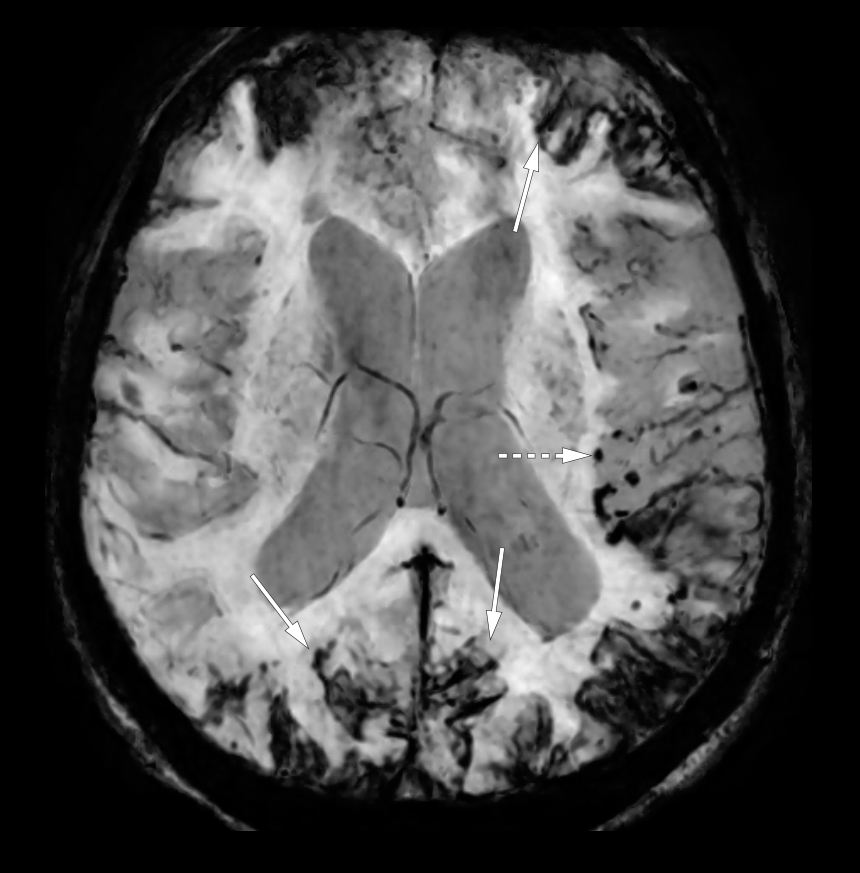

Susceptibilitetsvektede MR-bilder i aksialplanet viste utbredte hemosiderinavleiringer på hjerneoverflaten (heltrukne piler) forenlig med superficiell hemosiderose, tallrike mikrohemoragier i hjerneparenkymet (stiplet pil), de fleste subkortikalt i venstre hemisfære. Mikrohemoragier i forbindelse med en tidligere blødning er typisk for en amyloid angiopati.